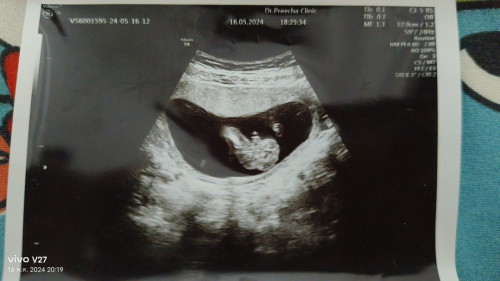

12วิคค่ะ ตอนไปหาหมอดิ้นเยอะมากค่ะ